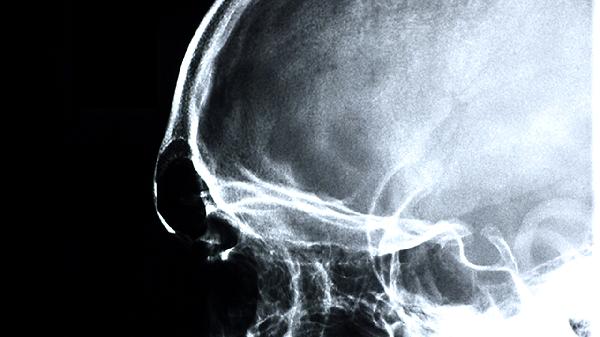

头晕目眩多与脑供血不足或自主神经功能失调有关。脑力宝丸具有补气活血功效,可改善内耳微循环和大脑氧供,缓解非器质性病变引起的眩晕症状。患者常伴有耳鸣、视物旋转等表现,持续严重眩晕需做头颅CT等检查。